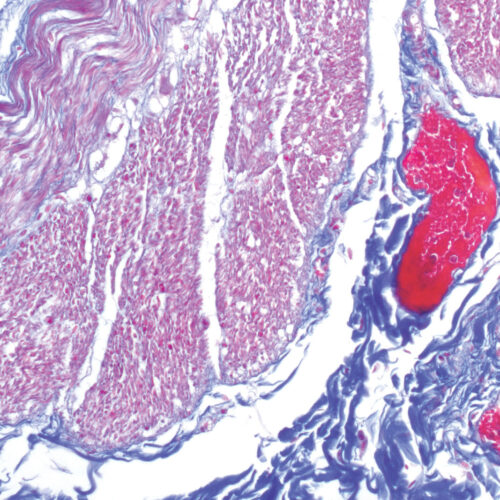

Azan Trichrome kit

Five-reagent kit for connective tissue staining according to Mallory. Used for visualization of muscle fibers, collagen, glial cells, glomerular cells and erythrocytes.